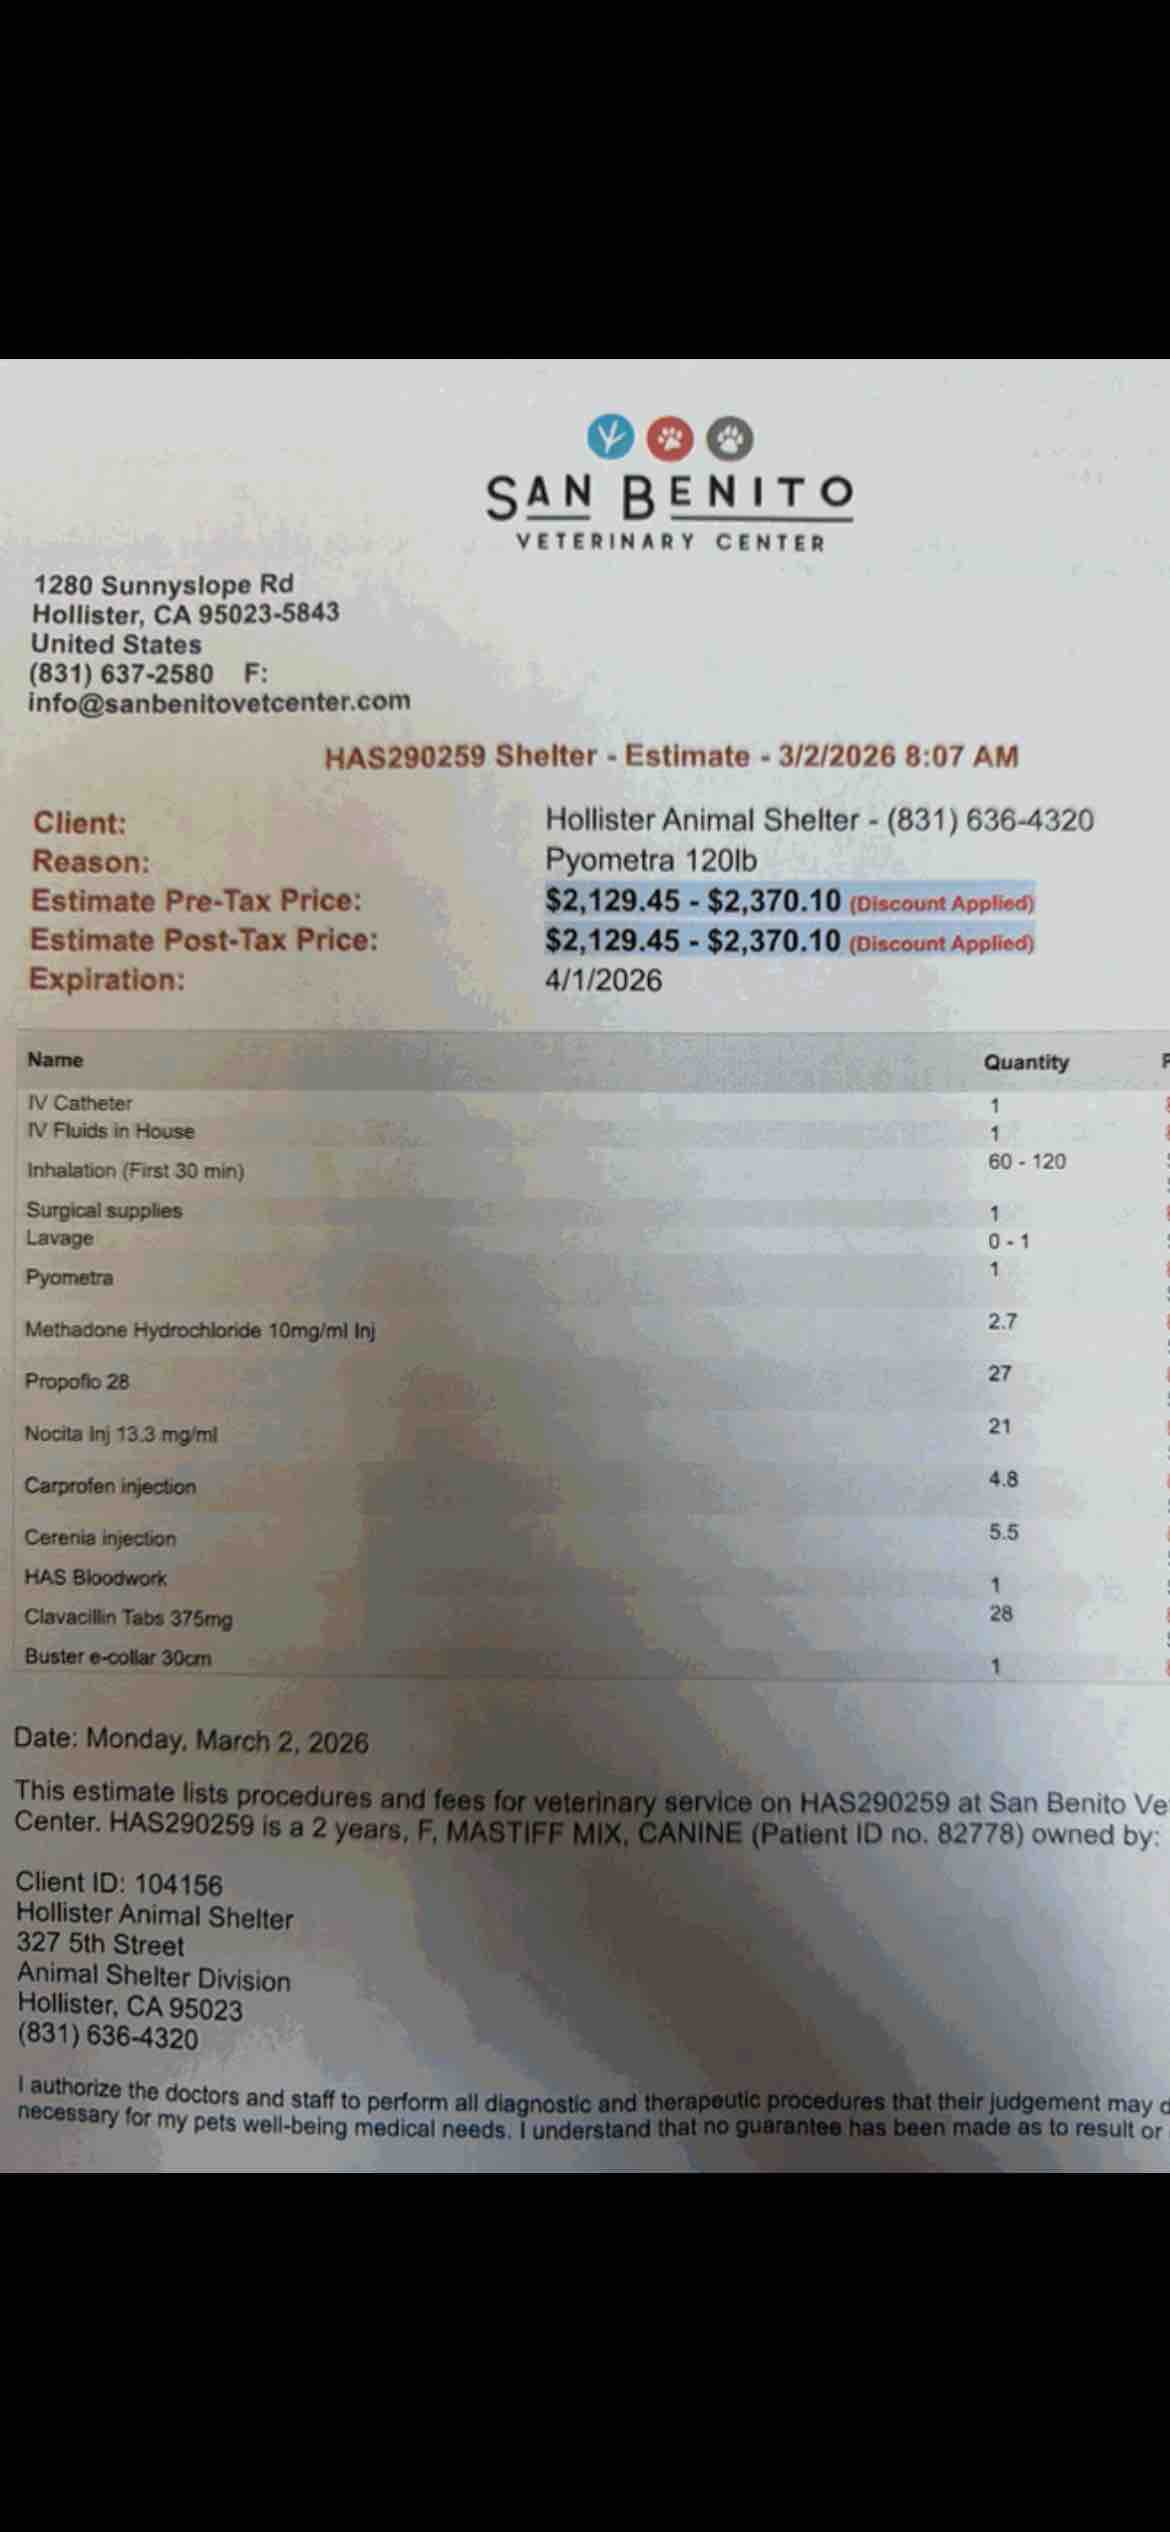

She came to us in crisis — a life-threatening pyometra infection and a ruptured gastrocnemius tendon that left her unable to walk. Two emergencies. One fragile little life. And a community that refused to look away.